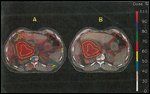

FIGURE 4

Energy Deposition Patterns

Charged particles such as protons and helium ions have also been used in the treatment of gallbladder and biliary cancers. In contrast to photons, the energy deposition patterns from charged particles are highly localized. This is due to a disproportionate absorption of the majority of their energy at the end of their track range-the so-called Bragg peak. The dose unit of charged particles is the Gray equivalent (GyE). Figure 4 demonstrates the energy deposition patterns of 15 MV photons, 9 MeV electrons, 30 MeV neutrons, 160 MeV protons, and Ir-192 seeds. Figure 5 compares dose distributions using IMRT techniques with conventional photon therapy and proton therapy in resected biliary cancer.

FIGURE 5

Radiotherapy Dose Distributions in Resected Biliary Cancer